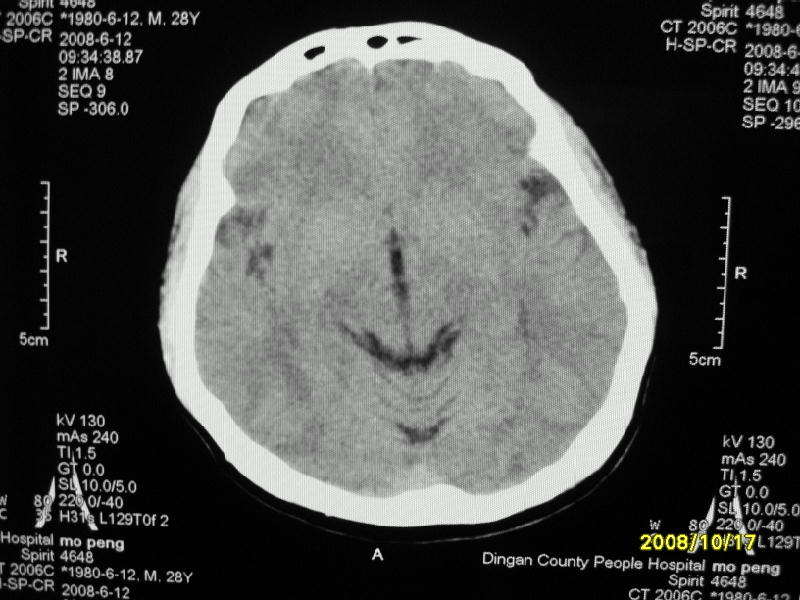

检查名称:     ct颅脑平扫           男     28岁

表现:左顶叶见斑点状致密影。边缘清,大小约0。3*1。0cm,余脑实质密度及灰白质结构示见异常。脑室系统大小,形态,密度未见异常。脑沟。脑裂。脑池未见异常密度影。中线结构无移位。

印象:左顶叶少许钙化灶

左顶叶见斑点状致密影。边缘清,大小约0。3*1。0cm,余脑实质密度及灰白质结构示见异常。脑室系统大小,形态,密度未见异常。脑沟。脑裂。脑池未见异常密度影。中线结构无移位。

印象:左顶叶少许钙化灶。